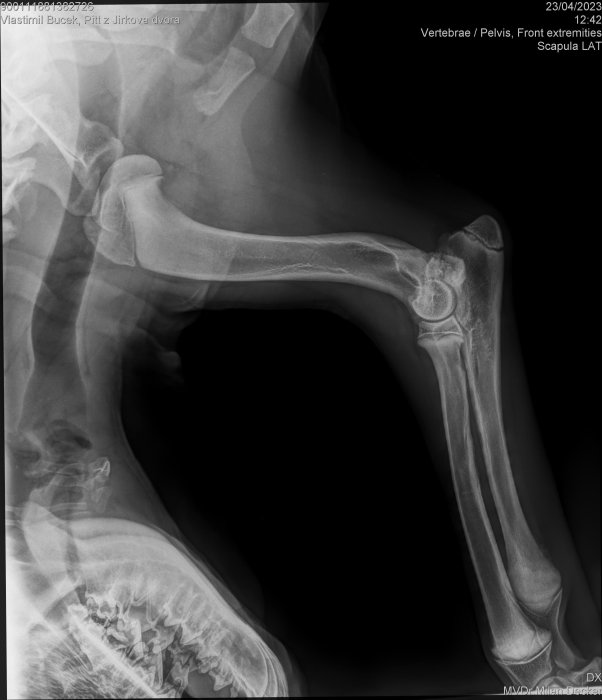

Jen mám pořád strach,aby jsme nemuseli znovu na operaci,je mě pejska líto a tyto rádoby CHS bych pozavíral,takový lidi by neměli chovat zvířata….